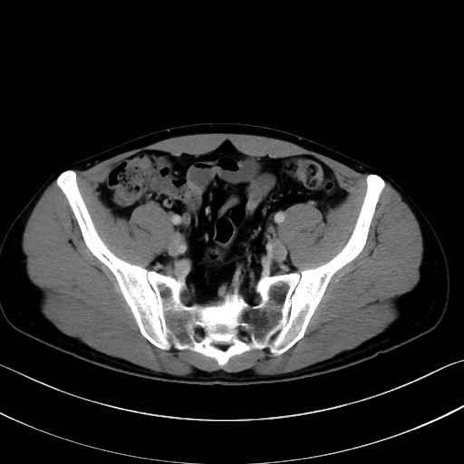

内閉鎖筋(obturator internus) のCT画像の解剖

内閉鎖筋 (Obturator internus)